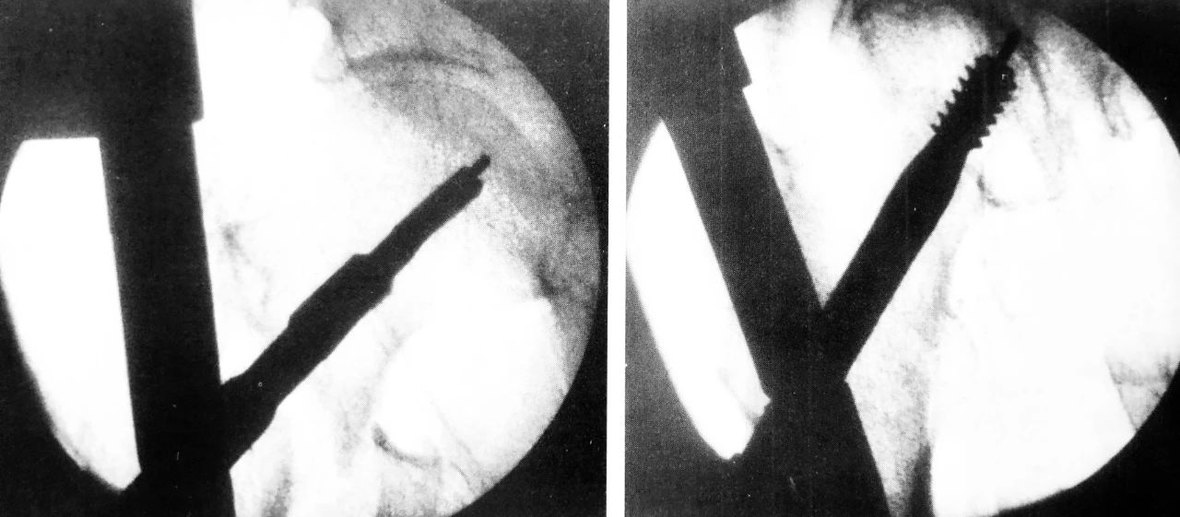

C 形臂下操作步骤,尖端开髓、插入导针

扩髓、主钉置入

正位拉力钉导针位置、侧位拉力钉导针位置

阶梯钻钻孔、正位拉力钉位置

侧位拉力钉位置、远端锁钉置入